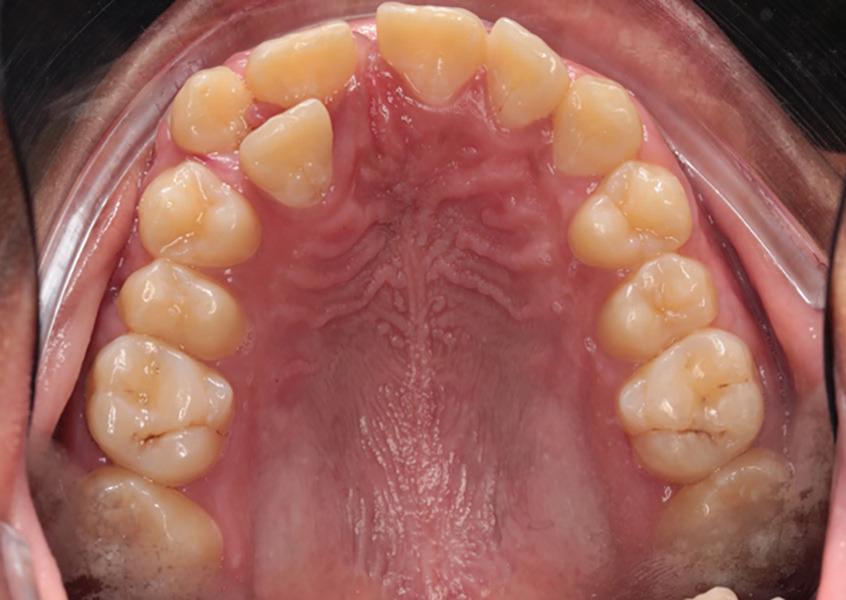

A healthy 10-year-old boy, accompanied by his mother, sought treatment of his mandibular right first molar because of pain in response to cold stimuli but reported no spontaneous pain in this tooth. Clinical examination revealed a carious lesion involving the occlusobuccal surfaces, and the tooth also appeared hypomineralized on the affected surfaces (Fig 1). The tooth responded positively to sensitivity tests, including the electric pulp test and cold test (Endo-Frost, Coltene), and there was no lingering pain or pain on percussion. A preoperative radiograph showed a large carious lesion extending to the pulp, incomplete root formation, and no pathologic periapical lesions (Fig 2). Therefore, the initial preoperative diagnosis was reversible pulpitis. The patient and parent were informed of possible pulp exposure, and VPT treatment after pulp exposure was explained in detail. Written consent for VPT was obtained from the parent.

of a mandibular right first molar with caries affecting the occlusobuccal surfaces, which appear hypomineralized.